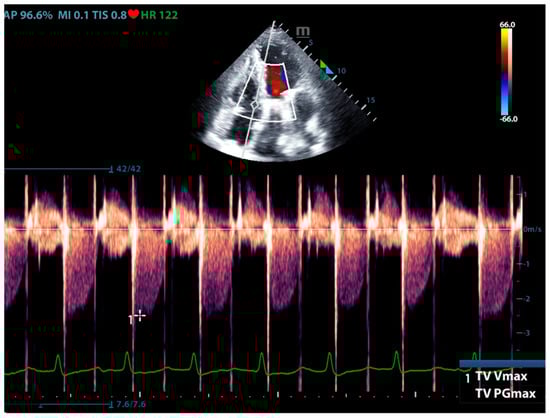

Physicians can assess pulmonary artery pressure quantitatively with point-of-care ultrasound. According to Bernoulli’s principle, the systolic pressure and diastolic pulmonary artery pressure can be estimated, respectively, by measuring the maximum regurgitation velocity of the tricuspid valve and the pulmonary valve. The maximum regurgitation velocity of the tricuspid valve (TVR Vmax) can be measured in the apical four-chamber view (Figure 6), and the maximum velocity of the pulmonary artery valve regurgitation (PVR Vmax) can be measured in the pulmonary artery long-axis view (Figure 7). Physicians can estimate pulmonary artery systolic pressure (PASP), diastolic pressure (PADP), and mean pulmonary artery pressure (mPAP) based on the ultrasound-measured TVR Vmax and PVR Vmax by the following formulas:

PASP = TVR Vmax2 + RAP(CVP)

PADP= PVR Vmax2 + RAP(CVP)

mPAP = 1/3 ∗ PASP + 2/3 ∗ PADP

Figure 6.

The ultrasound measurement of the maximum velocity of tricuspid valve regurgitation.

This can not only be used for the diagnosis of pulmonary hypertension but also for continuous and dynamic evaluation of pulmonary artery pressure [26]. It should be noted that the use of tricuspid regurgitation velocity to estimate pulmonary artery pressure with ultrasound Doppler has limitations. When the patient has severe tricuspid valve disease or severe right heart dysfunction, using the maximum tricuspid regurgitation velocity may underestimate the pulmonary artery pressure. Therefore, the evaluation of pulmonary hypertension should be combined with other ultrasound signs of the right ventricle, pulmonary artery, inferior vena cava, and right atrium.